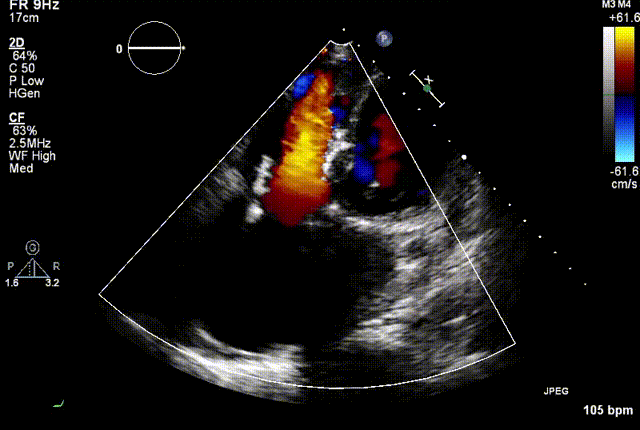

2021年12月7日,复旦大学附属中山医院葛均波院士团队完成的首批两例LuX-Valve Plus经血管三尖瓣置换患者顺利出院,从患者入院至出院仅历时一周时间,出院时患者状态恢复良好,复查心超三尖瓣无反流。

两例患者是都是外科手术高危的极重度三尖瓣反流的老年女性,反复下肢水肿、腹胀、纳差,活动耐力减退。一例患者风湿性心脏病,二尖瓣生物瓣置换术后,房颤,心超显示三尖瓣极重度反流(最大反流宽度15mm);另一例患者房颤,心超示三尖瓣极重度反流(最大流宽度23mm)。

结合术前CT评估结果,葛均波院士团队最终决定选用LuX-Valve Plus 50mm和55mm两种型号的瓣膜,并于2021年11月30日顺利完成LuX-Valve Plus经血管三尖瓣置换术,手术室即刻拔除气管插管,术后第二天转出心内科监护室,下床活动。术后患者三尖瓣反流症状得到显著改善,复查心超结果显示人工三尖瓣瓣膜支架固定稳定,瓣叶关闭形态未见异常,未见明显反流。

复查心超图

在本次救治性临床研究中,治疗的两例患者病因不同解剖结构复杂,均为极重度三尖瓣反流,手术最终都顺利植入了LuX-Valve Plus三尖瓣人工瓣膜。术后超声显示瓣膜支架固定稳定,反流症状显著改善,取得了良好临床治疗效果。